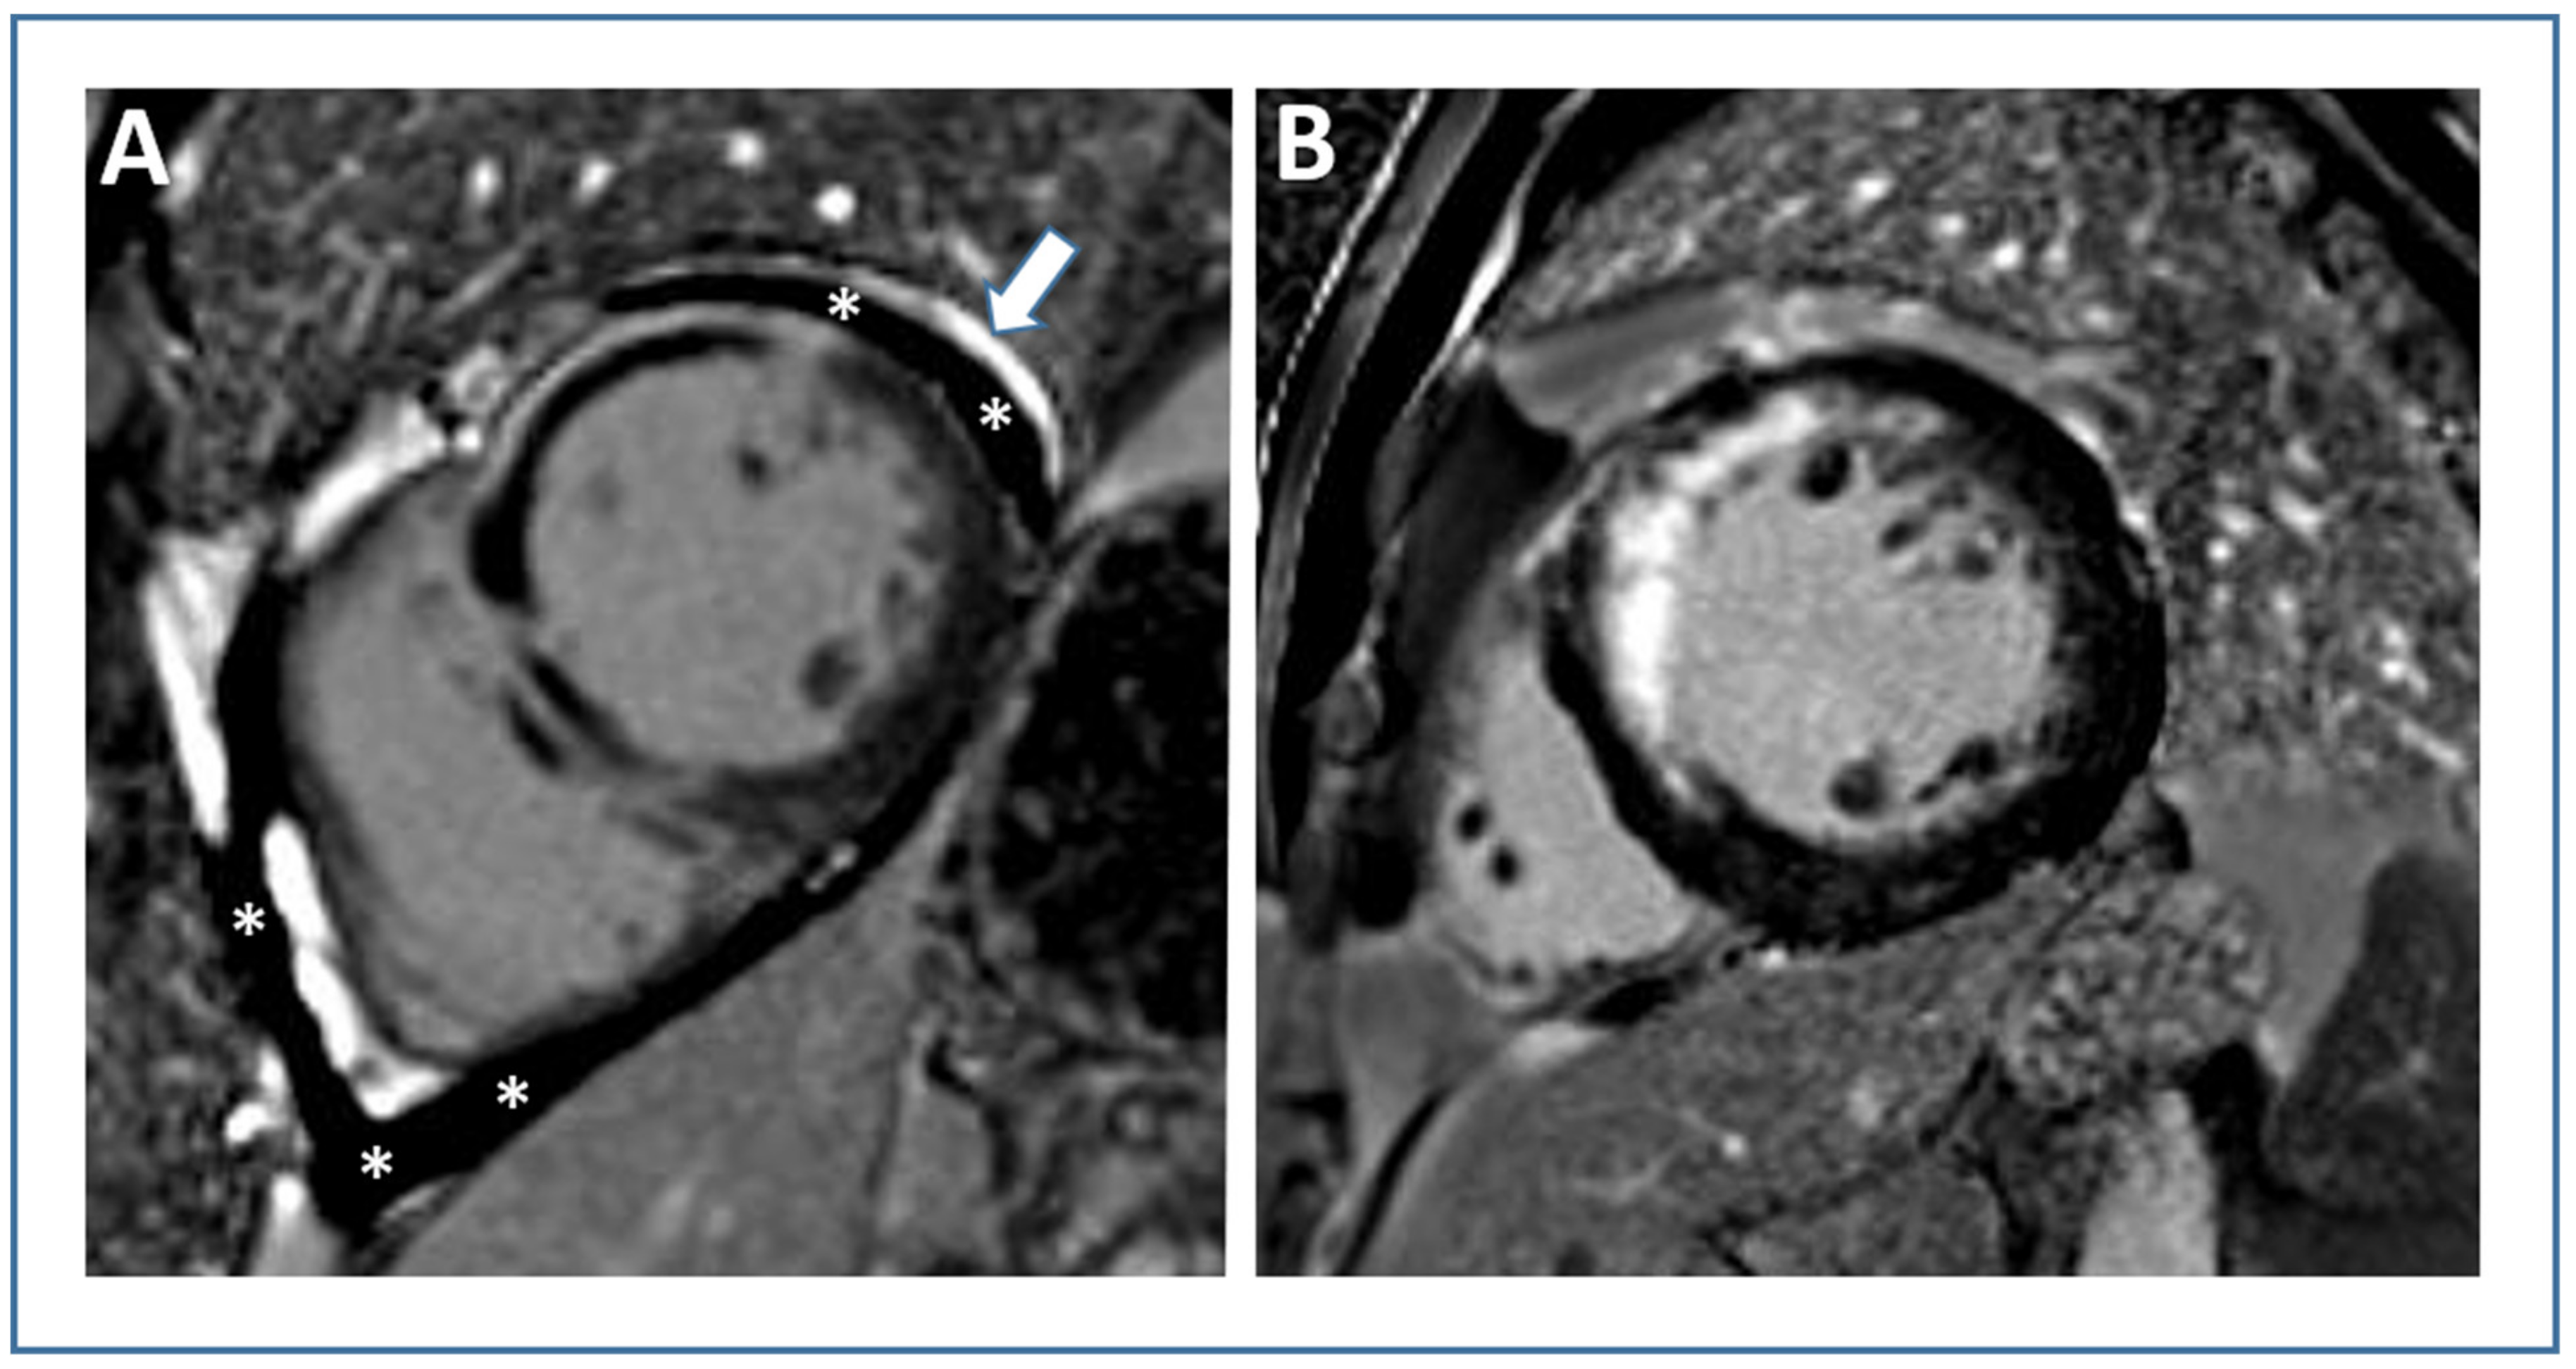

4. Myocardial Edema and Salvage

- Doulaptsis, C.; Goetschalckx, K.; Masci, P.G.; Florian, A.; Janssens, S.; Bogaert, J. Assessment of early post-infarction pericardial injury by CMR. JACC Cardiovasc. Imaging 2013, 6, 411–413. [Google Scholar] [CrossRef] [PubMed]

- Bogaert, J.; Masci, P.G.; Symons, R.; Janssens, S.; Doulaptsis, C. Impact of pericardial injury on inflammatory biomarkers early post myocardial infarction: A cardiovascular magnetic resonance (CMR) study. Int. J. Cardiol. 2015, 186, 139–140. [Google Scholar] [CrossRef] [PubMed]

- Biere, L.; Mateus, V.; Clerfond, G.; Grall, S.; Willoteaux, S.; Prunier, F.; Furber, A. Predictive Factors of Pericardial Effusion after a First Acute Myocardial Infarction and Successful Reperfusion. Am. J. Cardiol. 2015, 116, 497–503. [Google Scholar] [CrossRef]

- Jobs, A.; Eitel, C.; Poss, J.; Desch, S.; Thiele, H.; Eitel, I. Effect of Pericardial Effusion Complicating ST-Elevation Myocardial Infarction as Predictor of Extensive Myocardial Damage and Prognosis. Am. J. Cardiol. 2015, 116, 1010–1016. [Google Scholar] [CrossRef]